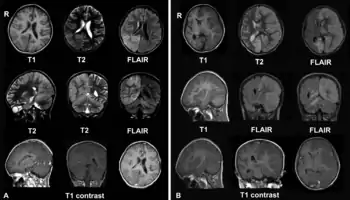

![]() Brain CT scan of a girl with Rasmussen's encephalitis. Brain CT scan of a girl with Rasmussen's encephalitis. | |

قد يتم التشخيص باستخدام الخصائص الإكلينيكية وحدها مع القيام باختبارات لاستبعاد باقي الأسباب المحتملة. يوضح تخطيط أمواج الدماغ عادة الخصائص الكهربية للصرع وبطء نشاط الدماغ في النصف الكروي المصاب، يوضح مسح المخ بالرنين المغناطيسي حدوث ضمور متدرج للنصف الكروي المصاب مع علامات الالتهاب أو تندب. يمكننا تأكيد تشخيص المرض من خلالخزعة دماغية إلا أنها ليست ضرورية بشكل معتاد.